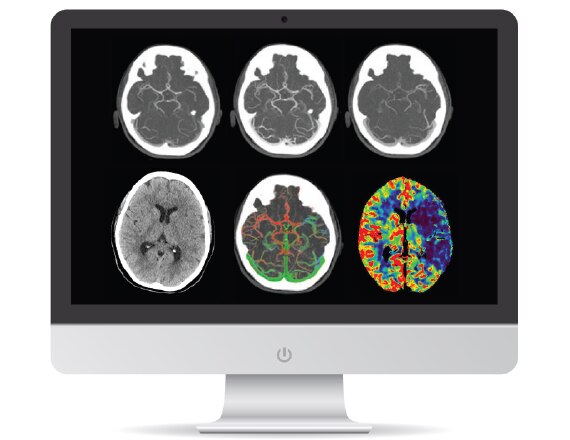

Un patient susceptible d'avoir souffert d'un AIT ou d'un AVC subit un examen général et neurologique suivi d'une imagerie cérébrale diagnostique, effectuée immédiatement à son arrivée afin qu'un traitement puisse être entrepris rapidement. 3 Un système d'acquisition optimal associé à des applications de flux de travail et à des protocoles conçus pour l'AVC permettent d'établir un diagnostic précis et rapide afin d'optimiser les résultats pour le patient.

Gamme de systèmes CT Revolution

Le système Revolution est capable d'acquérir une neuro perfusion et une angiographie (CTA) du cerveau en un seul examen pour une évaluation fonctionnelle et anatomique complète. Pour en savoir plus

Application FastStroke CT

Simplifie et organise les images CT pour une évaluation rapide des patients souffrant d'un AVC. Pour en savoir plus

Protocole Fast Brain avec HyperWorks

Fournit des informations structurelles et vasculaires avec une résolution améliorée et une caractérisation précise en 5 minutes. Pour en savoir plus